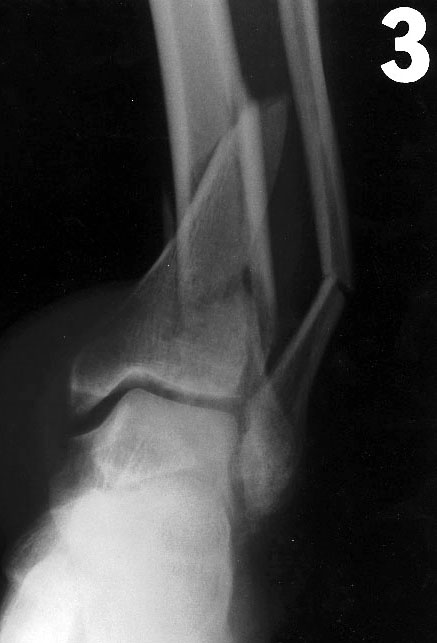

3/1/98 Rx Rt open ankle (distal tibia) fx - 27827 Open rx with tibia fixation, 20692 Ilizarov Multiplane external fixation, 11012 Debride open fx: skin, subq, fascia, muscle, bone